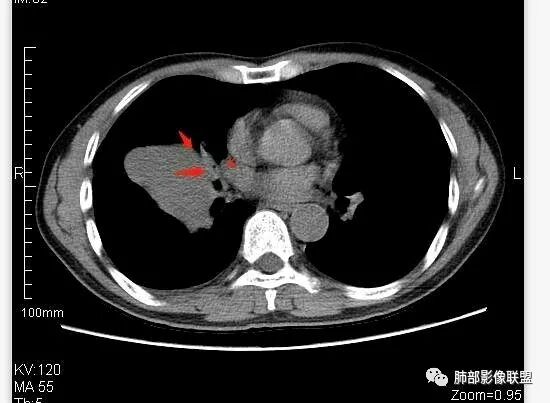

崇军:右侧中叶支气管与下叶支气管夹角处的肿块,支气管没有堵塞仅仅推移,不是支气管来源,纵隔来源也可以排除;跨叶,边界清,平扫无明显坏死,来源只剩下淋巴,血管与胸膜,如果是淋巴,纵隔未见其他淋巴结,淋巴瘤排除,巨淋巴增生症可能,血管来源,PSP可能,胸膜来源,SFT可能,这三者没有增强难鉴别。张帅:病灶边缘光滑,气管挤压呈贴边征,赞同王崇军老师观点:增大淋巴结,但同时需鉴别PSP及类癌。

南边:这类片其实很艰难Shelia:应该有个增强崇军:是的,如果没有老师您以前的讲述,一个肺门占位就发出去了风儿:肿块跨叶生长,边缘光滑,有膨隆有平直,支气管血管受压,病灶后方支气管似乎进入病灶后堵塞,与纵隔胸膜呈锐角,来源肺内-神经内分泌肿瘤?胸膜-SFT?血管-PSP?临近心包少量积液右侧胸腔少量积液是否与肿块有关

南边:中叶、下叶背段支气管推移

南边:有老师问为啥考虑中叶支气管受压?不是支气管来源的?

1、主体病灶在下叶

2、支气管腔还在,有移位

但是现在的片显示,其主体在下叶,中叶支气管壁由下朝上有推移

南边:下叶的支气管受压后移、变形

南边:病灶边界清,提示侵袭性弱,膨胀生长为主;这时候我们提示病灶不应该是支气管关系密切,提示间叶来源或胸膜来源